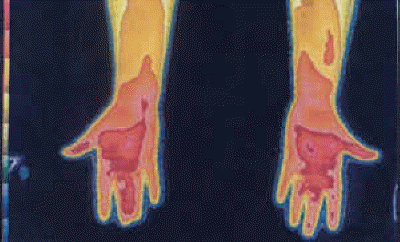

Venipuncture CRPS II Thermography Venipuncture CRPS II Damage to the Median Nerve.

Thermography of the Right Hand (a.k.a.) "Boxers Hand Deformity." CRPS of seven years duration due to right hand injury. Two years of unsuccessful operations at right carpal tunnel, and five years of immobilization of hand have resulted in "Boxers Hand Deformity" and ultimate amputation.